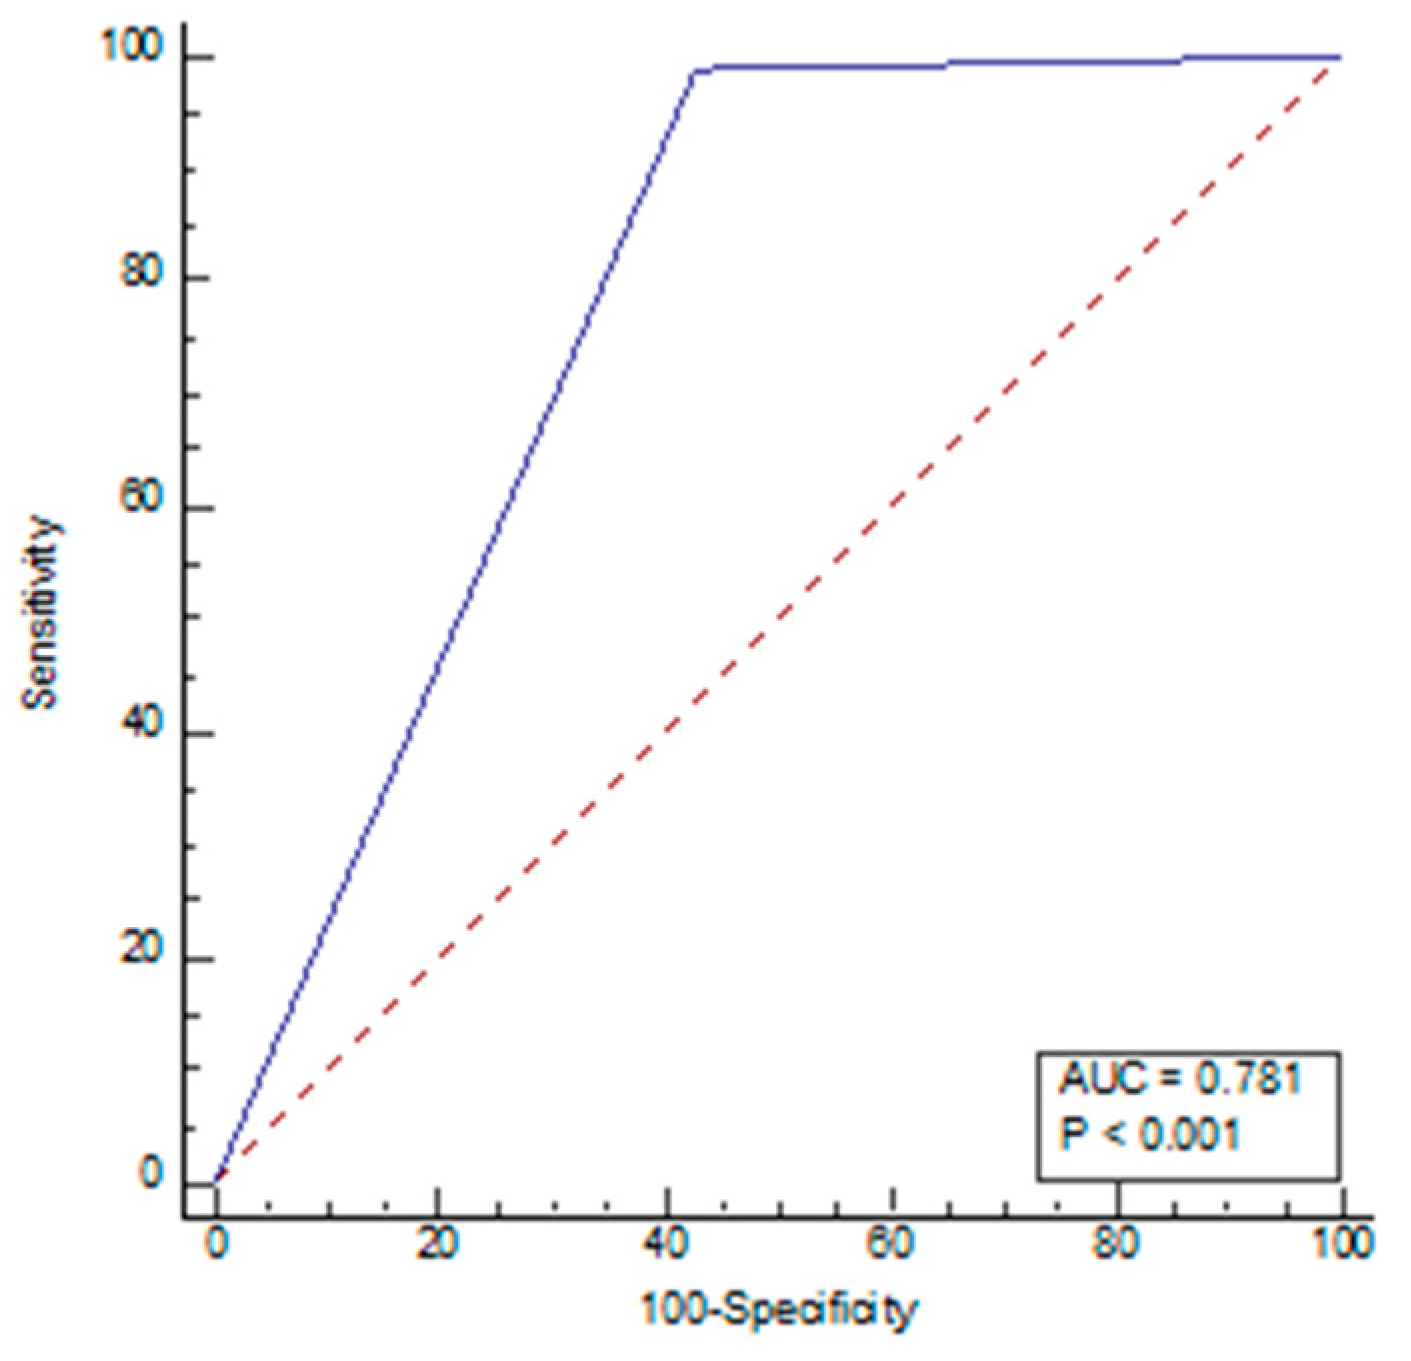

| Variables | Radiologists | AI *** |

|---|---|---|

| Sensitivity | 77.14% | 99.05% |

| Specificity | 98.21% | 57.14% |

| NPV * | 82.09% | 98.46% |

| PPV ** | 97.59% | 68.42% |

| Accuracy | 88.02% | 77.42% |